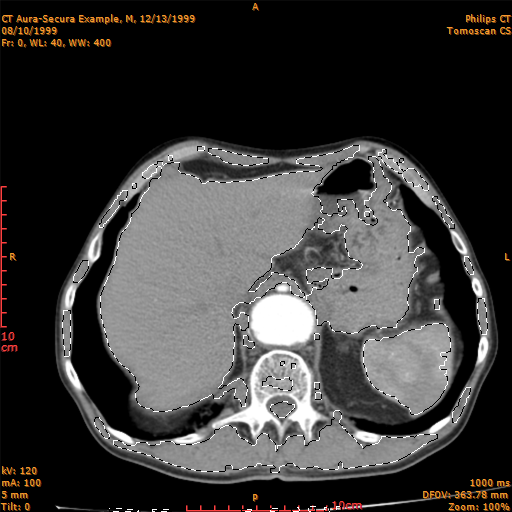

Eyedropper:

The eyedropper tool lets you select non-continuous areas of your image with similar intensity.

When you have selected an area with the eyedropper tool and before change tool, if you modify the tolerance the selected area is modified accordingly with the new tolerance.

You can adjust the tolerance with the menu command Selection Tolerance Dialog Box of the View menu.